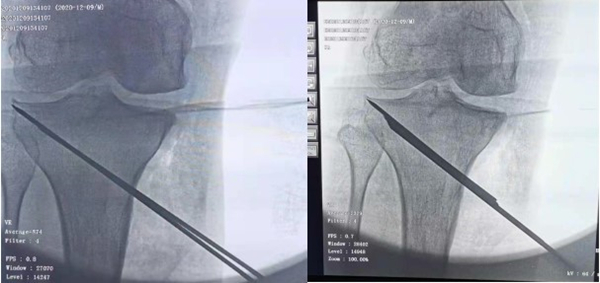

由王伟主任医师完成了左侧机器人辅助下胫骨内侧高位截骨术。手术通过比对术前CT数据与术中X片完成体表定位,标记克氏针均一次性准确到达设计好的截骨线,截骨撑开后以术前3D打印的个体化楔形模板确定撑开角度,减少了C型臂透视次数,术后患者膝关节疼痛缓解。